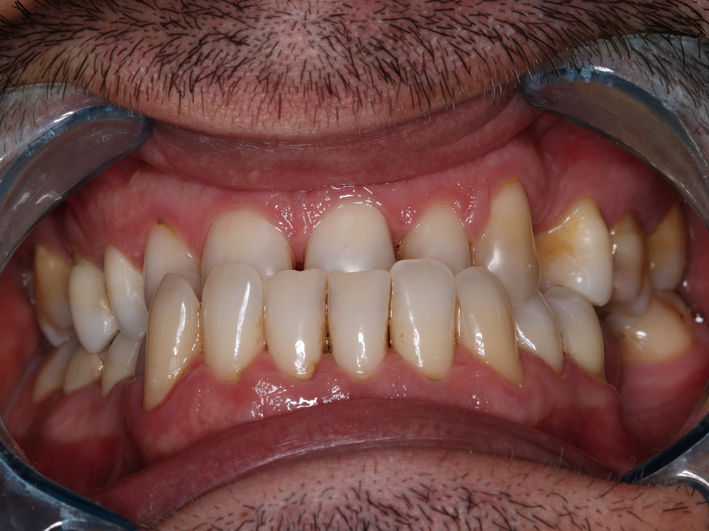

4. Tratament ortodontic pacient adult

O perioadă a existat preconcepția că tratamentul ortodontic este destinat doar copiilor sau adolescenților. Acest lucru nu este adevărat, putând fi realizat la orice vârstă. Particularitatea tratamentelor la pacienții adulți vine din prezența celorlalte patologii dentare și necesitatea colaborării cu celelalte discipline (chirurgie, parodontologie, endodonție, protetică).

În acest caz am realizat retratament endodontic 2.6, extracție 4.6, tratament ortodontic, inserare implanturi în locul dinților lipsă 1.6, 3.6, 4.6, coroane dentare din zirconiu multilayer înșurubate pe implanturi.